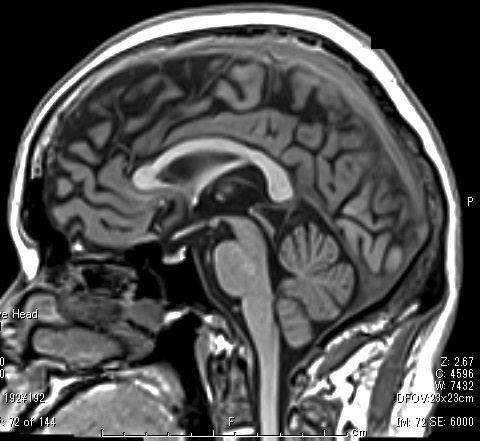

MRIとは核磁気共鳴画像(Magnetic Resonance Imaging)の略です。

MRI検査は、非常に強力な磁石でできた筒状の装置に入り、磁気や電波を利用して人体のさまざまな断面を撮影する検査です。X線撮影やCTのようにX線を使用していないため、放射線被ばくはありません。

当院では1.5テスラ超伝導式装置が導入されています。

検査空間も従来のMRI装置よりも広くなり、より開放感のある検査環境となっているため、閉所恐怖症の患者様や体格の大きな患者様もより快適に検査を受けられます。

また、静音性の技術が搭載されているので、騒音の少ない検査を受けられます。

頭部